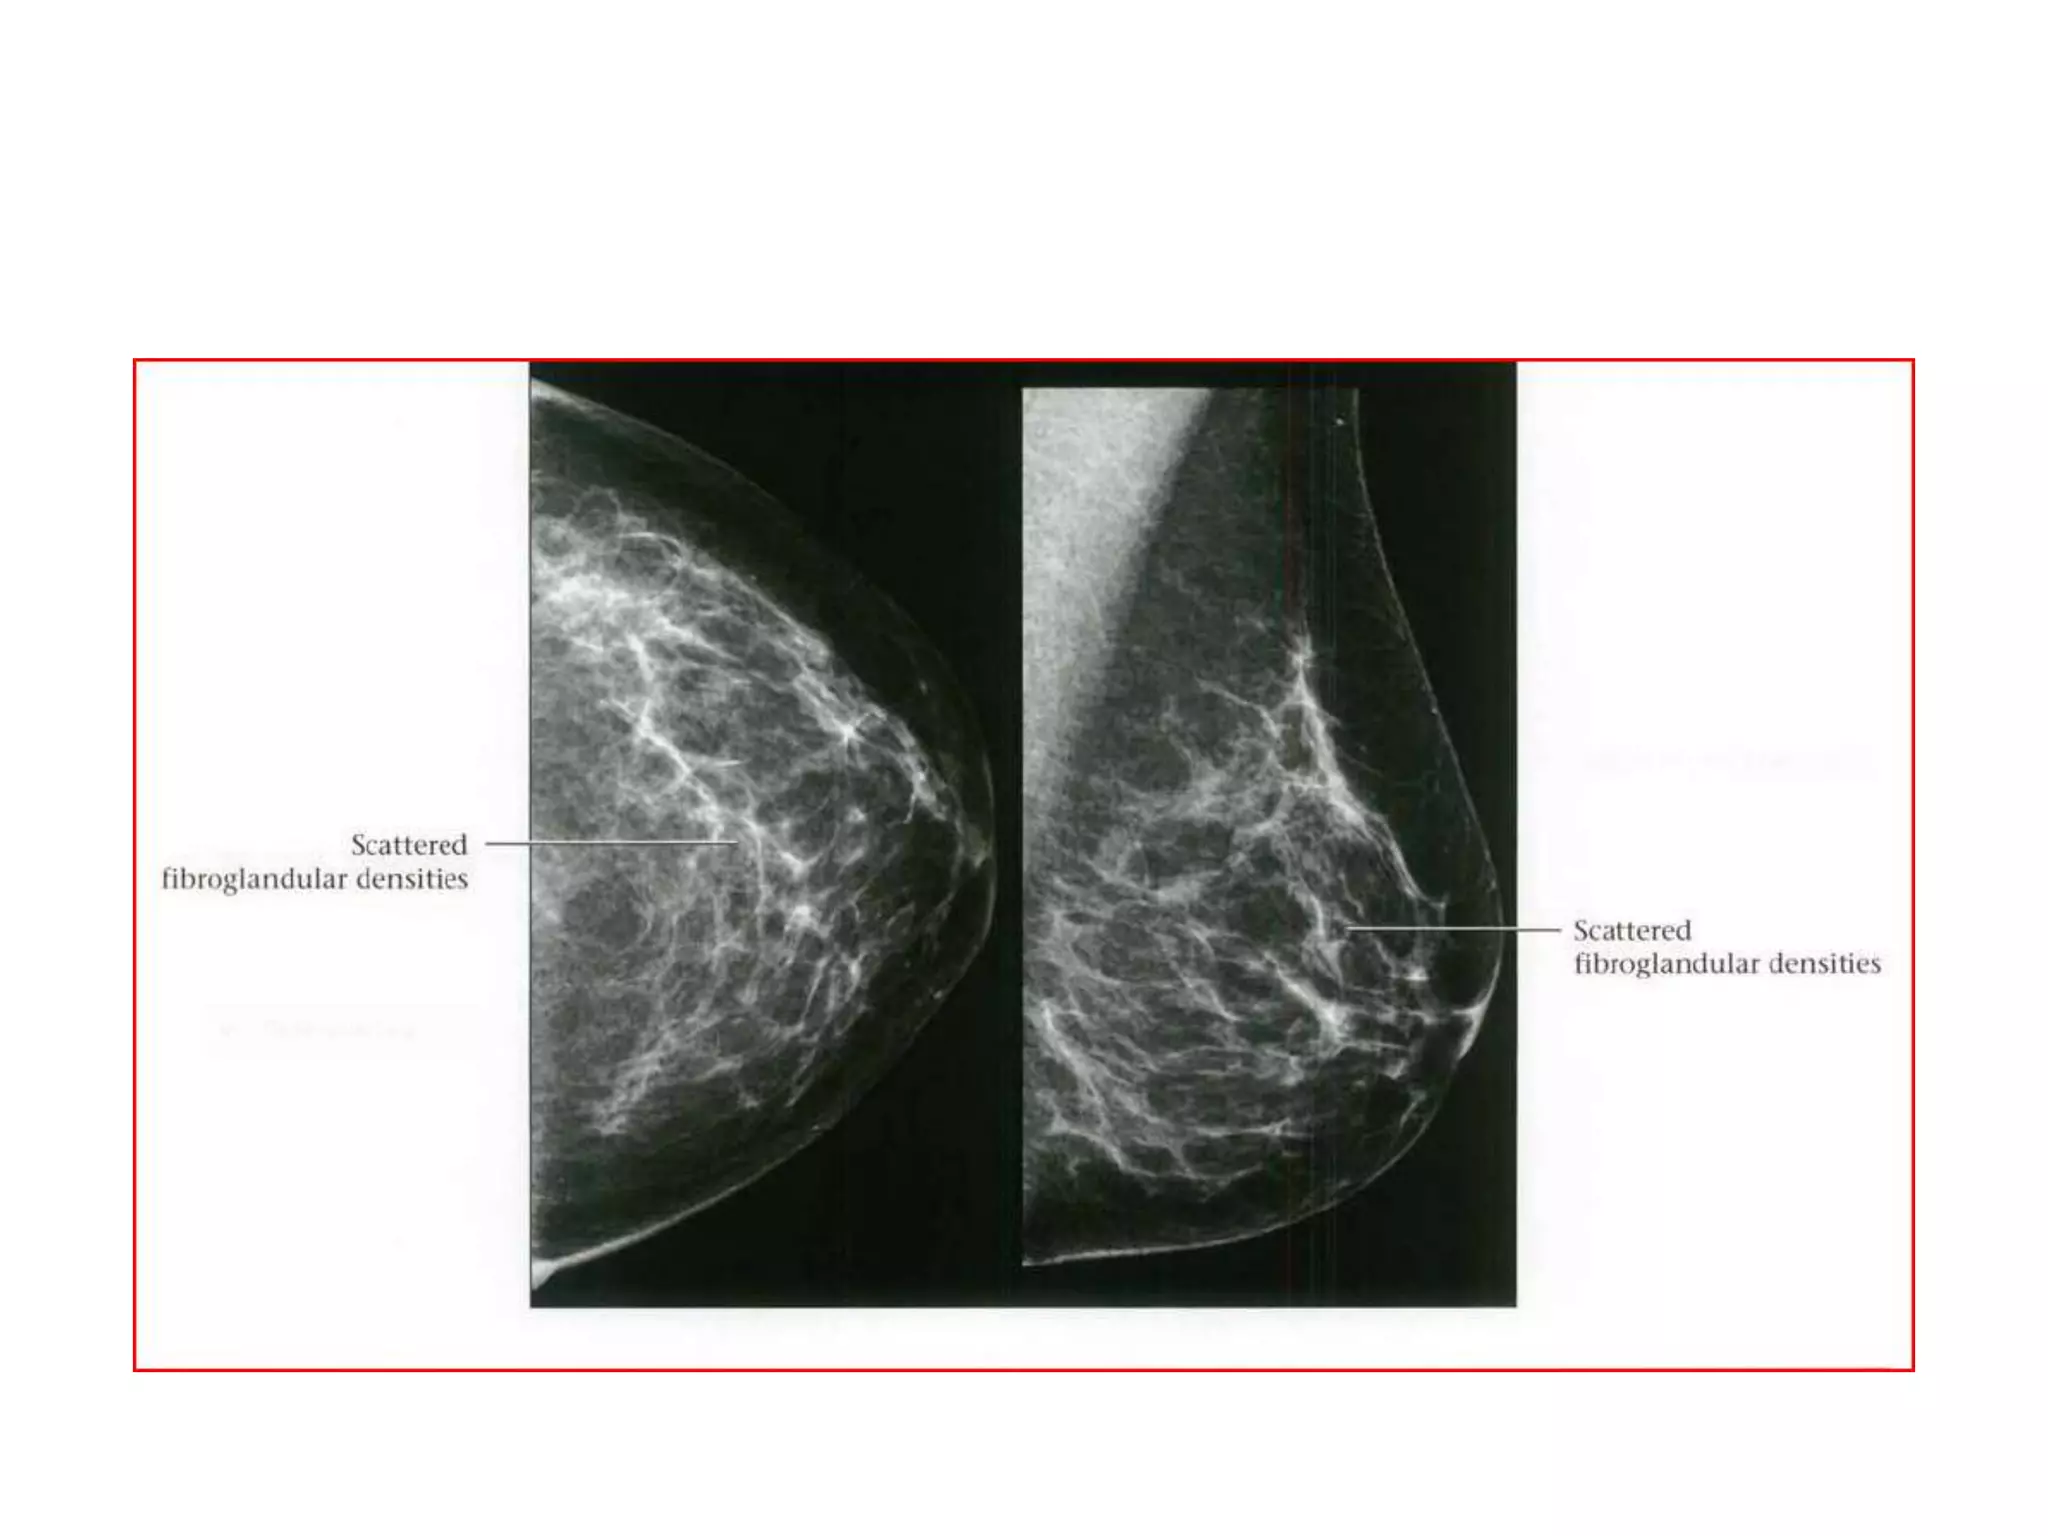

BI-RADS BREAST COMPOSITION

• The American College of Radiology Breast

Imaging and Reporting Database System (BIRADS)divides breast composition into four

categories:

• 1) almost entirely fat,

• 2) scattered fibroglandular densities

(approximately 25-50% glandular),

• 3) heterogeneously dense (51-75% glandular),

• 4) extremely dense (greater than 75% glandular).